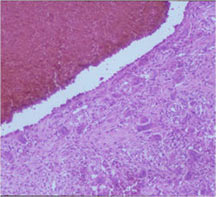

Microscopic Pathology

- Tumor has cyst-like spaces divided by septa

- Septa composed of atypical, bizarre, malignant appearing spindle cells with atypical nuclei and atypical mitotic figures

- Osteoid production is scant, focal and lace-like

- High degree of nuclear atypia, cellular pleomorphism, normal and atypical mitotic activity

- In highly necrotic tumors that appear grossly as blood clot, malignant cells may be separated in a background of necrotic and bloody debris and may be difficult to identify.